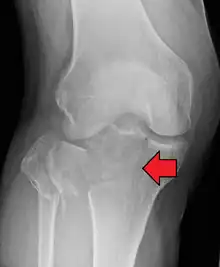

Lipohemarthrosis (presence of fat and blood from bone marrow in the joint space after an intraarticular fracture) seen on X-ray in a person with a subtle tibial plateau fracture

Lipohemarthrosis due to a tibial plateau fracture

A tibial plateau fracture seen on X-ray